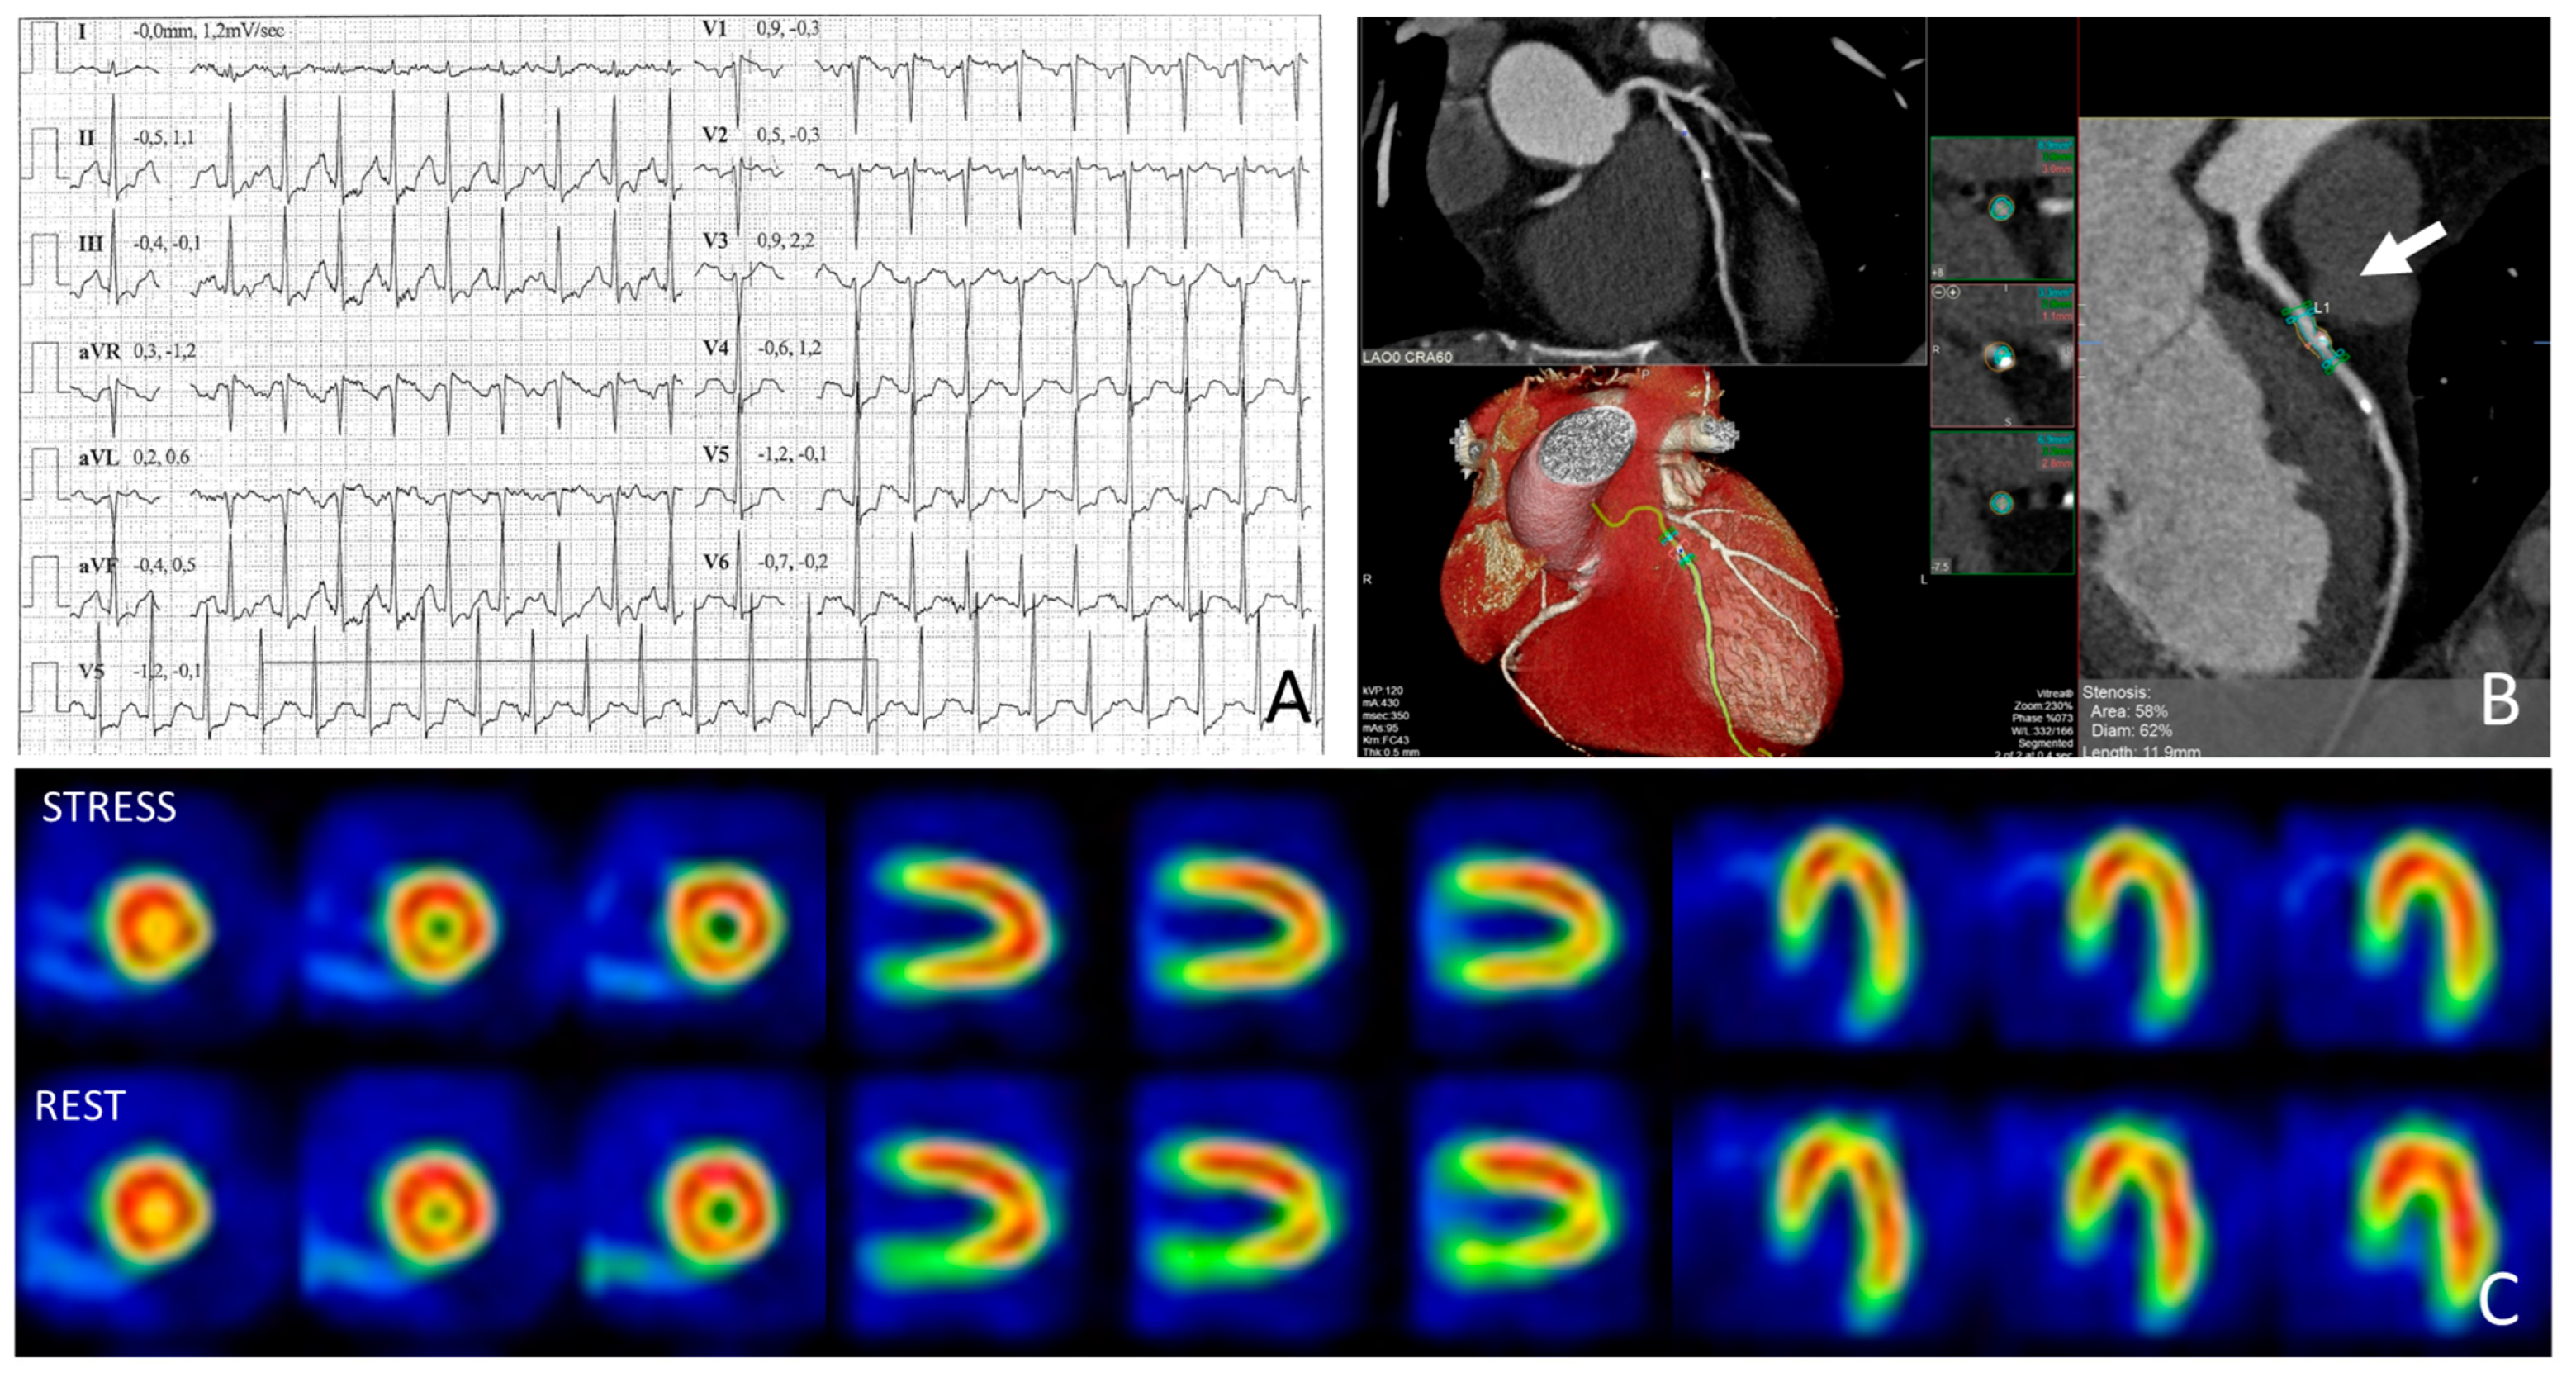

4.1. Athlete with Positive Exercise Testing and Moderate Coronary Stenosis

4.2. Athlete with Positive Exercise Testing and Myocardial Bridging